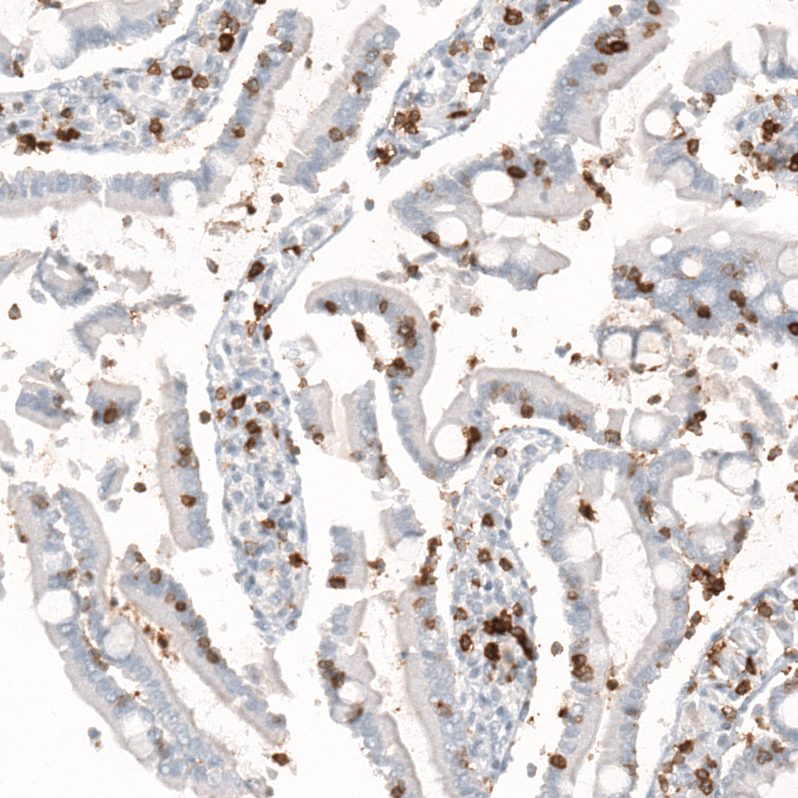

Immunohistochemistry analysis in human lymph node and skeletal muscle tissues using AMAb91783 antibody. Corresponding CD5 RNA-seq data are presented for the same tissues.